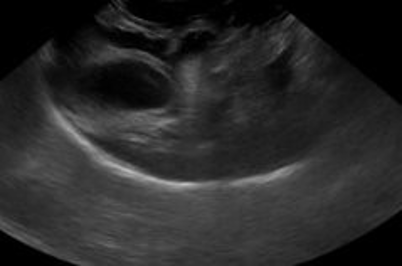

A halo or double rim effect to the gall bladder can occur almost immediately after insult due to portal hypertension and vascular permeability changes.1 Sensitivity of this marker is 93% with a specificity of 98%.5

It is important to note that if ultrasound is performed on these patients, mass like hematomas have been noted especially in the liver due to the intraparenchymal bleeding (Figure 2). It is a clinical judgment call based on all the information of the case that will help you determine if this is a patient with a hemoabdomen due to a primary bleeding mass that needs surgical stabilization or if this is an anaphylactic patient with hepatic hematomas who needs rapid medical stabilization. These mass like lesions, if they are hematomas, should resolve over time on recheck ultrasounds (Figure 3).